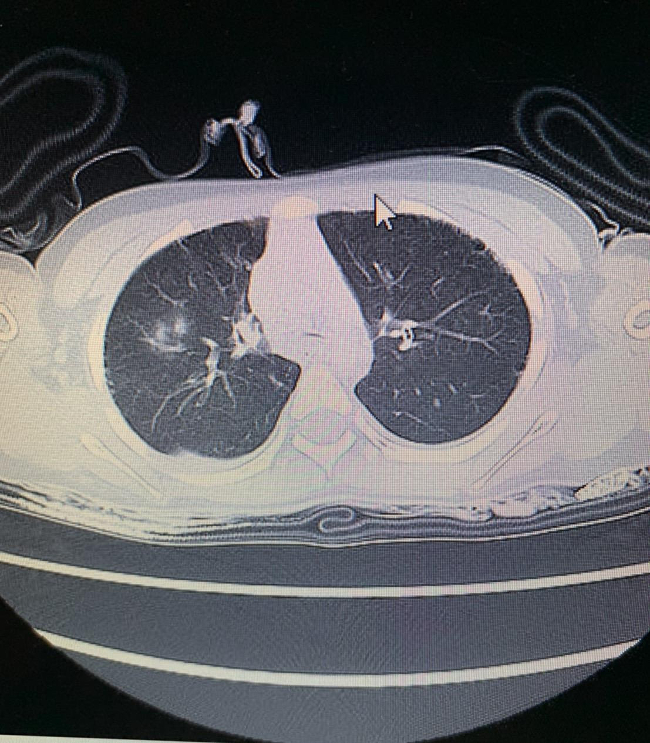

優空君の死亡時、肺のCT写真

これは、遺族にのみ開示された優空君の死亡時、医療センターにより撮影されたCTスキャンのデータの一部である。

これについて、私が見た時の感想は、肺に水がほとんど入っていないということだ。

ただ、溺水は、肺の水だけでは判断が難しいものだし、専門家に鑑定を依頼することにした。

医師や医療関係者による所見は下記のようなものであった。

「溺水とするには、縦隔条件のCTデータでは足りない」

「溺水ありきで作られている乱暴なものだ」

ということであった。また、医療関係者によれば、

「心臓と心臓を覆う心外膜の間に液体が大量に貯留することによって心臓の拍動が阻害された状態である心タンポナーゼが確認できるため、胸に強い衝撃を受けた可能性がある」

というものであった。

一方、この液体については、水に長く浸かることで、体中の穴から水が入って溜まることがあるので、何とも言い難いという意見もあった。

また、これについてはAbemaの番組サイドにも提供し、番組で精査した専門家にも鑑定を依頼したが、同様に、これのみで溺水とするには足りないという見解であった。また、肺の陰について、通常溺水判断のものとは大きく異なり、白い部分があまりに少ないという見解がある。

本人記録を確認したところ、学校の記録には、「気管支が弱い」という記録があった。つまり、このCT画像では、気管支が弱く肺胞ができたのか、水が入ってできたのか不明瞭と言わざるを得ないということだろう。